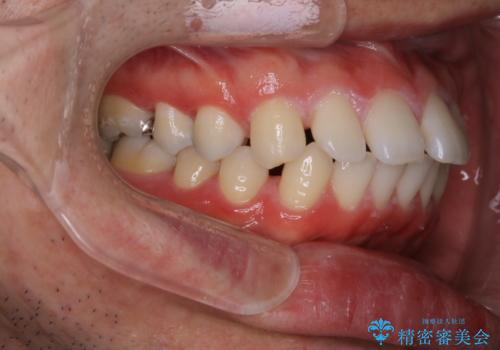

- 全体的に歯と歯の間に隙間があるのが気になるとのことで来院されました。インビザラインでの矯正治療をご希望されました。

隙間については、前歯と奥歯に多数あります。また、上下前歯は、外側に少し倒れているため隙間を閉じつつ、前歯を内側に引っ込めて並べることになりました。